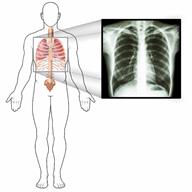

An outline of a person's body and an image of an X-ray of the person's chest.

• Le pedirán que se quede quieto mientras le toman las imágenes.

• Le pedirán que tome una respiración profunda y que la contenga durante algunos segundos.

• La máquina de radiografías tomará una imagen de su pecho. No va a doler.

• Posiblemente se tomen más imágenes desde otros ángulos. Si no puede estar de pie, podrían pedirle que se recueste.